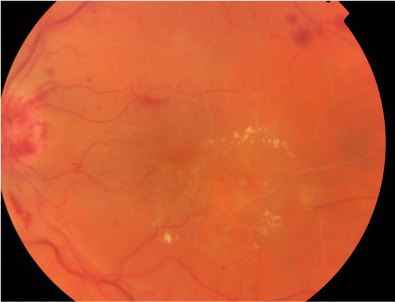

At baseline, best corrected visual acuity (BCVA) was 0.8 Snellen equivalent at right eye (RE) and 0.3 Snellen equivalent in the left eye (LE). Intraocular pressure was 14 mm Hg in both eyes. Slit-lamp examination of the anterior segment revealed nuclear sclerosis. Clinical examination of the retina revealed a nonproliferative diabetic retinopathy in both eyes, associated with the presence of clinically significant DME with hard exudative deposition in the LE (Figure 1). Central retinal thickness (CRT) on OCT was 223 μm and 551 μm in RE and LE, respectively, at baseline. Fluorescein angiography (FA) (Figures 2 and 3) disclosed more clearly the presence of the diabetic retinopathy with DME in the LE. The patient was advised to undergo intravitreal injection of ranibizumab.

Figure 2. Composite fluorescein angiography in the early phases showing a nonproliferative diabetic retinopathy.

Figure 3. Late-phase fluorescein angiogram at higher magnification displaying the extension of the clinically significant macular edema.